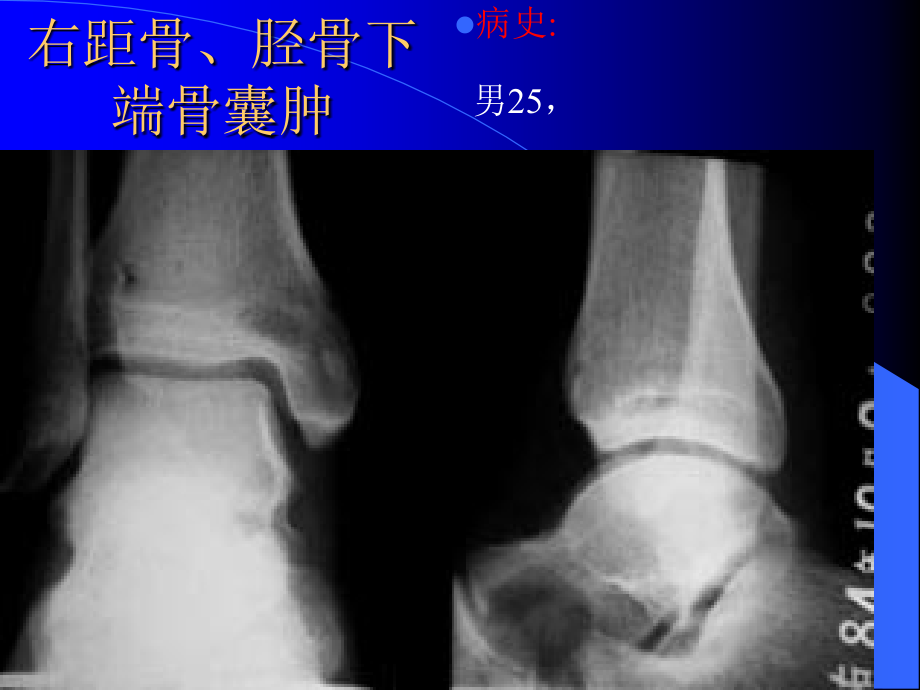

,单击此处编辑母版标题样式,*,单击此处编辑母版文本样式,第二级,第三级,第四级,第五级,右腓骨下端骨囊肿,病史,:,男,21,,,右距骨、胫骨下端骨囊肿,病史,:,男,25,,,左侧跟骨骨巨细胞瘤,病史,:,男,26,,,右距骨囊肿,病史,:,男,17,岁 发现右侧中背外侧肿瘤,3,年,右足背外侧触及,2.5*2CM,质硬肿物,无压痛。,右跟骨动脉瘤样骨囊肿,病史,:,女,18,,,双测跟腱腱鞘囊肿侵入跟骨,病史,:,男性,,20,岁。双侧足跟疼痛,3,个月。影像学:双侧跟骨的跟腱附着处见类圆形骨破化区,边界清楚,周边轻度骨硬化。手术病理:双测跟腱腱鞘囊肿侵入跟骨,左脚拇指甲下外生骨疣,左胫腓骨下段混合型骨血管瘤,病史,:,女,20,,,右侧肋骨骨软骨瘤,病史,:,男,31,,,肋骨骨软骨瘤,病史,:,女,23,,肋骨骨软骨瘤,(,少见生长方式,误诊),肋骨骨软骨瘤,病史,:,男,1,岁,10,月,肋骨骨软骨瘤,(,少见生长方式,误诊),右侧第五肋骨嗜酸性肉芽肿,病史,:,男性,,34,岁。右侧胸痛,40,天,无咳嗽,无胸闷气短。检查:右背部叩击痛,无明确压痛点。肺部听诊无异常。影像学表现:,CT,示右第五肋骨长圆形局灶性骨破坏区,大小约,1*1.5,厘米,,CT,值约,63HU,左右,局部肋骨轻微膨大。病灶边界清楚,有轻度硬化环。手术病理:右侧第五肋骨嗜酸性肉芽肿。,胸椎肋骨转移瘤,病史,:,女性,,50,岁,一年前发现肝癌,胸背部疼痛,2,个月。,左侧第九肋骨转移瘤,病史,:,女性,,45,岁,舌癌术后,1,年余体检。征象:左侧第九肋骨骨质破坏,周围可见软组织影。,左侧第一肋骨骨巨细胞瘤,右肋骨硬化型单发骨髓瘤,病史,:,女,57,,,硬化型单发骨髓瘤,病史,:,男,32,,右第,8,后肋骨硬化型单发骨髓瘤,左侧第,7,后肋嗜酸性肉芽肿,病史,:,男性,4,岁,左背部发现肿物半月余。,肋骨骨软骨瘤,病史,:,女,23,,肋骨骨软骨瘤,(,少见生长方式,误诊),肋骨骨软骨瘤,病史,:,男,1,岁,10,月,肋骨骨软骨瘤,(,少见生长方式,误诊),胸骨腺泡样软组织肉瘤,伴脊柱骨转移,病史,:,男,,58,岁,主诉:前胸部肿胀,疼痛,2,个月。缘于,2,月前无诱因出现前胸部隐痛,活动时明显并感前胸部肿胀,症状逐渐加重。胸痛为局限性,并向背部放射,咳嗽时加重。无发热、咯血、咳痰。,T,:,36.5,摄氏度,,P:80,次,/,分,,R:18,次,/,分,,BP:16/10Kpa,。,PE:,前胸骨体处隆起,皮肤无发热,肩部压痛明显。入院后,患者症状加重,并发现腰部疼痛,胸部,CT,示胸骨肿块,脊柱,CT,示多发性骨质破坏,本周氏旦白阴性,血红旦白正常,肾功正常。我院诊断:,1.,多发性骨髓瘤。,2.,淋巴瘤。,3.,转移瘤。望各位专家给予会诊,并提出宝贵意见,.,左肘右膝关节骨软骨瘤病,多发外生骨疣,病史,:,男,42,,,多发骨纤维瘤病,病史,:,男,36,,,非骨化性纤维瘤病,病史,:,男,8,岁,,多发骨血管瘤,病史,:,女,28,,腰,3,附件、右侧骶骨、左侧髂骨多发骨血管瘤,双上肢软组织及骨多发性血管瘤病,病史,:,女,,22,岁,,右骶髂骨网织细胞肉瘤,病史,:,女,55,,,骨转移瘤,病史,:,女,52,,宫颈癌,腰椎,4,、骨盆、股骨硬化型骨转移瘤,多发硬化型骨转移瘤,病史,:,男,78,,前列腺癌,骨盆、肋骨、腰椎、股骨多发硬化型骨转移瘤,颅骨、肋骨多发性骨髓瘤,病史,:,女,59,,,多发性骨髓瘤,病史,:,女,46,,颅骨、肋骨、右肱骨多发性骨髓瘤,颅骨多发性骨髓瘤,病史,:,女,63,,,多发性骨髓瘤,病史,:,男,63,,头、骨盆、肋骨、股骨多发性骨髓瘤,多发骨髓瘤,病史,:,女性,,58,岁。反复发作腰背部疼痛,2,年余,加重,10,天。本周蛋白阴性。影像学:颅骨多个类圆形低密度破坏区。腰椎明显骨质稀疏伴椎体压缩。骨盆骨质稀疏,右侧坐骨膨胀性破坏。骨髓穿刺及病理:多发骨髓瘤,多发性骨髓瘤,病史,:,男性,,44,岁。腰痛进行性加重,5,个月。尿本周蛋白阳性。影像学:颅骨多发破坏区,脊椎椎体骨质稀疏,椎体压缩,骨盆及双侧股骨颈多发圆形骨破坏区。骨髓穿刺病理:多发性骨髓瘤,颅骨骨盆多发性骨髓瘤,病史,:,女,52,,,嗜酸性肉芽肿,-,多发,病史,:,男性,26,岁,多发骨纤维异样增殖症,病史,:,女,32,,左侧半身多发骨纤维异样增殖症,右股骨干上段骨囊肿,病史,:,女,22,,,左股骨下段动脉瘤样骨囊肿术后,病史,:,男性,,13,岁,左大腿下段肿痛,1,月余。征象:左股骨下段肿瘤切除术后,见局部骨质缺损,周围见骨膜反应,核素扫描见局部浓集。,软骨肉瘤,病史,:,男,52,,右股骨中段软骨瘤术后两年恶变软骨肉瘤,右股骨下段软骨肉瘤,病史,:,男,52,,,股骨下段软骨肉瘤,病史,:,男性,,18,岁,,股骨中下段骨肉瘤(层状骨膜反应,成骨型),病史,:,男,19,,,骨肉瘤,+,恶性纤维组织细胞瘤,病史,:,男,22,岁,左股骨下段混合型骨肉瘤,+,恶性纤维组织细胞瘤,溶骨性左股骨下段骨干骨肉瘤,病史,:,男,26,岁,,成骨性左股骨骨干骨肉瘤,病史,:,男,21,,,成骨性右股骨骨干骨肉瘤,病史,:,男,38,,,成骨性左股骨骨干骨肉瘤,病史,:,男,22,,,成骨性右股骨骨干骨肉瘤,病史,:,男,42,,,右侧股骨下段骨旁骨肉瘤,病史,:,男,30,,,左股骨中上段骨旁骨肉瘤,病史,:,男,21,,,左股骨纤维组织肉瘤、肺转移,病史,:,男,41,岁 患者左髋下胀痛,左大腿上部可触及体积较大的软组织肿块,局部温度略高。,左侧股骨中上段尤文氏瘤,病史,:,男,14,,,右侧股骨尤文氏瘤,病史,:,男,21,,,右侧股骨尤文氏瘤,病史,:,男,29,,,骨肉瘤,+,恶性纤维组织细胞瘤,病史,:,男,22,岁,左股骨下段混合型骨肉瘤,+,恶性纤维组织细胞瘤,肺癌股骨混合型骨转移瘤,病史,:,女,63,,,右股骨白血病骨受侵改变,病史,:,男性,3,岁,,右股骨白血病骨受侵改变,右侧股骨白血病骨受侵改变,病史,:,男,3,,,右股骨中段内侧深面肌肉间血管脂,病史,:,女性,38,岁右大腿疼痛已个月。,PE,:右大腿中上,1/3,内侧压痛。,左大腿中上段皮下脂肪瘤,病史,:,女,37,岁 左大腿内后侧可扪及一大小约鸭蛋块影,活动度尚可,边缘欠清楚。,B,超:左下肢末见明显占位性病变。征象,:,左大腿内侧示有一类圆形肿块,呈短,T1,稍长,T2,信号,边缘清楚,与周围肌层有明显分界,.,轴位示病变呈楔形,基底位于外侧,.MR,压脂见病变信号基本消失,.,左股骨下前区滑膜肉瘤,病史,:,女,60,,,左股骨纤维肉瘤,病史,:,M 41,岁患者,80,年初无诱因左股隐痛,,83,年发现局部肿块,三次手术证实为纤维肉瘤,左股骨下段动脉瘤样骨囊肿术后,病史,:,男性,,13,岁,左大腿下段肿痛,1,月余。征象:左股骨下段肿瘤切除术后,见局部骨质缺损,周围见骨膜反应,核素扫描见局部浓集。,右股骨上段嗜酸性肉芽肿,病史,:,男性,,34,岁,右锁骨骨干骨肉瘤(成骨型),病史,:,男,35,,,右锁骨远端转移癌,.,肺转移癌,.,病史,:,F 42,左乳腺癌术后右锁骨转移放疗后复查,右侧胸锁关节重叠处桨细胞肉瘤,病史,:,女性,,56,岁。左胸锁关节上方肿块,逐渐增大,4,个月,肿块,4*5*3,厘米,质硬,活动度差,无明显压痛。影像学:右侧胸锁关节重叠处一软组织肿块,密度均匀,边界欠清。手术病理:桨细胞肉瘤,骨纤维异样增殖症,病史,:,左侧锁骨外段肩胛骨骨纤维异样增殖症,左锁骨单发溶骨性骨髓瘤,病史,:,男,50,,,肩胛骨下角骨软骨瘤,病史,:,男,11,,,右侧肩胛骨外生骨疣,右肩胛骨骨软骨瘤,右侧肩胛骨骨软骨瘤,病史,:,男性,,75,岁。慢性血吸虫性肝病入院,常规胸片检查。影像学:右侧肩胛骨初见一类圆形不均匀高密度肿块,边界清楚。手术病理:右侧肩胛骨骨软骨瘤,左侧肩胛骨骨巨细胞瘤,病史,:,男,22,,,右肩胛骨软骨瘤恶变为软骨肉瘤,病史,:,男,31,,右肩胛骨肿块,4,年,无红肿痛,近两月肿块发展迅速,疼痛明显。,右侧乳腺癌左肩胛骨转移,病史,:,女性,50,岁,右侧乳腺癌术后,2,年,现觉左肩疼痛。征像:左肩胛骨喙突及关节盂明显骨质破坏,关节间隙不规则。,左肩关节滑膜肉瘤直接侵犯肩胛骨,病史,:,男,9,,,韩雪柯氏病,病史,:,韩雪柯氏病(不同时期改变),右肱骨上端软骨母细胞瘤,病史,:,男,,43,岁,右肩痛,伴活动受限,有外伤史,.,右肱骨上段软骨母细胞瘤,病史,:,女,74,,,左肱骨上端骨纤维异常增殖症,病史,:,F 12,左上臂疼痛,3,月余,左肱骨上段骨囊肿,病史,:,男,5,,,恶性骨巨细胞瘤,病史,:,男,23,,左肱骨上端恶性骨巨细胞瘤,右肱骨上端骨巨细胞瘤,病史,:,女,22,,,左肱骨上段骨巨细胞瘤,骨巨细胞瘤(生长活跃期),病史,:,男,13,,左肱骨上端骨巨细胞瘤(生长活跃期),右肱骨软骨瘤恶变为软骨肉瘤,病史,:,男,50,,右肱骨软骨瘤恶变为软骨肉瘤(,14,年前病理为软骨瘤),右肱骨肉瘤,病史,:,男,12,右上臂肿物,2,月余,右肱骨上端骨肉瘤(混合型),病史,:,男,22,,,左肱骨上段骨肉瘤(溶骨型),病史,:,男性,42,岁,,右肱骨上端骨肉瘤(溶骨型),病史,:,女,27,,,右肱骨上端骨肉瘤(成骨型),病史,:,女,15,,,右肱骨上端骨肉瘤(溶骨型),左肱骨上端骨肉瘤(成骨型),病史,:,男,27,,,右肱骨头原发淋巴肉瘤,病史,:,女,18,,,右肱骨上段软骨母细胞瘤,病史,:,女,74,,,右肱骨嗜酸性肉芽肿,病史,:,女性,,10,岁,左肱骨上端骨肉瘤(混合型),病史,:,女,14,,,右肱骨上端骨肉瘤(混合型),病史,:,男,12,,,软骨母细胞瘤,+,非骨化性纤维瘤,病史,:,男性,18,岁,左肱骨软骨母细胞瘤,+,非骨化性纤维瘤,右侧肱骨上段骨软骨瘤,软骨母细胞瘤,+,非骨化性纤维瘤,病史,:,男性,18,岁,左肱骨软骨母细胞瘤,+,非骨化性纤维瘤,左肱骨中上段动脉瘤样骨囊肿,病史,:,男,13,,,左肱骨上段动脉瘤样骨囊肿,病史,:,男,48,,,右肱骨中段软骨瘤恶变为软骨肉瘤,病史,:,男,18,,右上臂包块,20,年,无疼痛,近日肿块发展迅速,疼痛明显。,右肱骨骨干溶骨性骨肉瘤,病史,:,男,52,岁,,混合型左肱骨骨干骨肉瘤,病史,:,女,48,左肱骨骨干骨肉瘤(溶骨型),病史,:,男,56,,,左肱骨骨干骨肉瘤(溶骨型),病史,:,男,21,,,骨纤维肉瘤,病史,:,男,26,左肱骨骨干纤维母细胞型溶骨型肉瘤,左肱二头肌肌间海绵状血管瘤,病史,:,女性,16,岁患者,4,岁时左肘关节活动受限,无红、肿、热,无明显外伤史,,PE,:左上臂肿胀,有压痛,实质感,肿物移动度差,边界不清。,骨纤维异样增殖症多囊性表现,病史,:,女,16,,左肱骨骨纤维异样增殖症多囊性表现,骨纤维异样增殖症伴病理骨折,病史,:,男,40,,左肱骨骨纤维异样增殖症伴病理骨折,右肩胛骨及肱骨软骨肉瘤,病史,:,男,30,右肩胛部肿痛,5,月,左腋下淋巴水瘤,病史,:,女性,,11,岁。左腋下肿块,2,年,突然增大伴疼痛,10,天。,B,超示腋下囊性肿块。检查:左腋下,7,厘米肿块,囊状,有压痛。影像学表现:左腋下囊状肿块,有分叶和间隔,病变边界清楚,密度均匀,,CT,值,35HU,左右。病变向软组织间隙侵入并突向肺尖。增强扫描示病变间隔轻微强化。手术病理:囊性淋巴管扩张症(淋巴水瘤)。,右肱骨恶性纤维组织细胞瘤,病史,:,男,71,,,尤文氏瘤,病史,:,男性、,14,岁 右上肢肿痛三月征象:右肱骨中段呈纺缍状增大,髓腔及部分骨皮质呈筛孔样破坏,周围见葱皮样骨膜反应,两端可见骨膜三角,周围可见软组织肿块。,骨纤维异样增殖症伴病理骨折,病史,:,男,40,,左肱骨骨纤维异样增殖症伴病理骨折,左肘关节骨软骨瘤病,病史,:,男,20,,,右肱骨下端嗜酸性肉芽肿,病史,:,男性,,5,岁,左肘关节骨软骨瘤病,病史,:,男,20,,,左肘关节骨软骨瘤病,病史,:,男,20,,,桡骨上端骨囊肿,病史,:,男,28,,,右尺骨骨软骨瘤,病史,:,男性,,18,岁,,左侧尺骨尤文氏瘤,病史,:,男,15,,,右尺骨恶性纤维组织细胞瘤,病史,:,女,30,,,左侧尺骨白血病骨受侵改变,病史,:,男,3,,,(左前臂)幼年性纤维瘤病,病史,:,女,5,岁 主诉:左前臂肿物一年余 患儿,1,年前其父母无意中发现左前臂肿大,触及一肿物,患儿无诉不适,左手功能运动正常。患儿母亲末在意,无任何治疗。近来患儿父母发现患儿左前臂肿物有所增大,伴有不适感,故来我院门诊求治,拟诊左前臂肿物待查?,骨巨细胞瘤(生长活跃期),病史,:,未提供病史,左尺骨远端骨巨细胞瘤(生长活跃期),左挠骨远端软骨粘液样纤维瘤,病史,:,女,,20,岁,,右下颌骨造釉细胞瘤切除术后复发,病史,:,男性,27,岁,12,年前在我院行右下颌骨造釉细胞瘤切除术后植骨。,右下额骨单纯骨囊肿,动脉瘤样骨囊肿,病史,:,男性,,10,岁。右下颌骨渐大,无痛性肿块,1,个月检查:肿块质软,有波动感,穿刺抽出血性液体。影像学表现:右下颌骨近中线囊性膨胀性骨破坏,呈吹气球样改变,临近牙根受挤压。手术病理:动脉瘤样骨囊肿,左下额骨含齿囊肿,病史,:,男,42,,,左下颌骨根尖囊肿,右下额骨囊肿,病史,:,男,26,,,右下颌牙骨质瘤,病史,:,女,,31,岁现病史:一年前发现右下前牙区一花生米大小肿物,无疼痛发热。生长缓慢,近,2,个月来,生长较快,长至核桃大小,无自觉不适。体格检查:,T:36.5C R:18,次,/,分,P:72,次,/,分,Bp:18/12Kpa,专科检查:面部不对称,左腮腺区肿胀,压痛明显,包块质硬,固定无动度,边界不清,表面光滑。初诊:,1.,右下颌,4-1,根尖囊肿,2.,左腮腺急性腮腺炎征象:右下颌,4-1,根尖处下颌骨内有一类似圆形低密度影,边界清,明显硬化缘,大小约,2.32.6cm2,右下颌,4-1,根尖包含在囊腔内。,左上颌牙骨质母细胞瘤,病史,:,男,,21,岁现病史:左上颌部肿大,几天后肿物隐痛。经一系列消炎,抗感染治疗均无效。近一周来肿物疼痛在吃饭时剧烈,以至不能吃较硬的食物。体格检查:,T:37C P:80,次,/,分,R:20,次,/,分,BP:14/10Kpa,专科检查:面部对称,张口不受限。肿物表面粘膜颜色正常,触痛,质地较硬。初诊:,1.,左上颌骨化纤维瘤,2.,左上颌肿瘤体查 征象:,CT,片示左侧上颌牙槽骨髓腔密度明显增高,瘤骨生长,约,22.5cm2,骨皮质破坏,内侧牙龈肿胀。左侧上颌窦密度增高。,